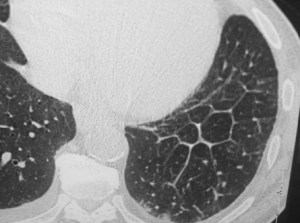

En el corte de TC de tórax con contraste intravenoso del mismo paciente vemos la rotura aórtica (flecha verde), un hemotórax bilateral –algo más cuantioso en el hemitórax izquierdo- (flechas azules) y un hematoma mediastínico (flecha naranja).